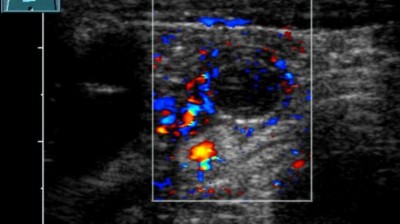

Ein Knubbel in der Wange – an welche Diagnose denken Sie?

Nach wiederholten Besuchen bei Kinder-, HNO- und Zahnärzten steht nun die 11-jährige Patientin vor Ihnen. Sie leidet seit zwei Jahren unter belastungsabhängigen Schmerzen beim Kauen. Nachdem eine vorausgegangene Sonographie und ein vergrößerter Lymphknoten eine Raumforderung im M. masseter vermuten lassen, sehen Sie nun diese MRT-Bildgebung.